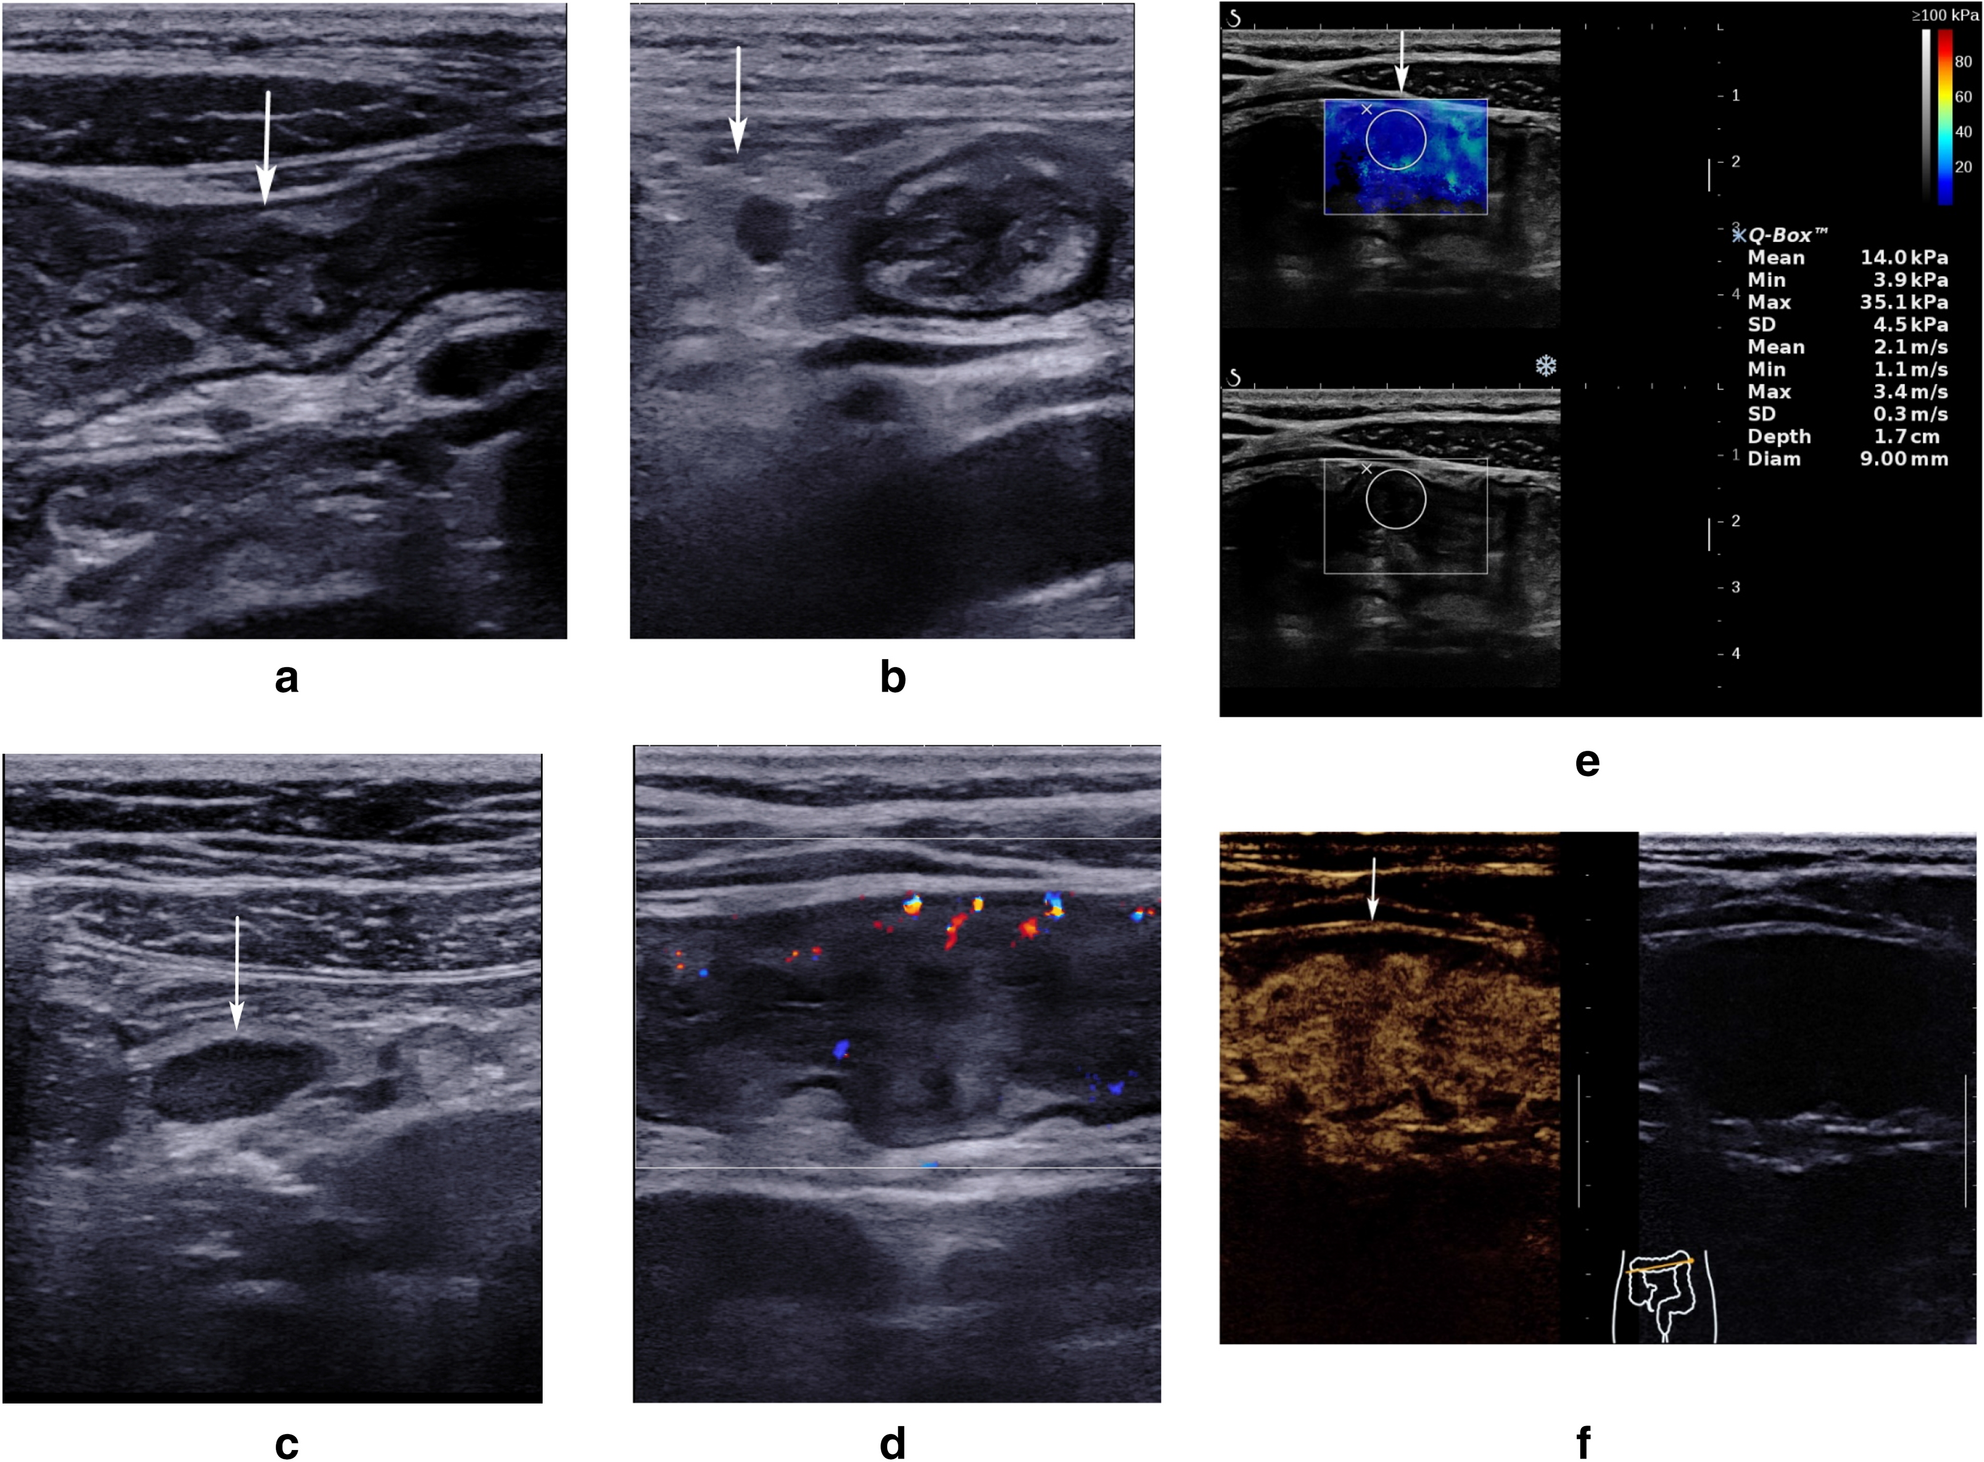

Figure 1

Examples of ultrasonic findings. Male, 18y, recurrent gastrointestinal bleeding for 1 year, CDAI: 336. (a) White arrow indicates thickening of the colon wall. (b) White arrows indicate mesenteric fat thickening. A lymph node can be detected in the thickened mesenteric fat. (c) White arrow indicates mesenteric lymphadenopathy. (d) The vascularization in the colon wall was scored to be Limberg II. (e) White arrow indicates that the anterior wall of the colon is soft, and the shear wave elastography of the anterior wall is homogeneous blue with a mean SWV of 2.1 m/s. Figure 1f. White arrow indicates a transmural homogeneous enhancement (TE homogeneous), and stratification of the intestinal wall still remains (SE presence).